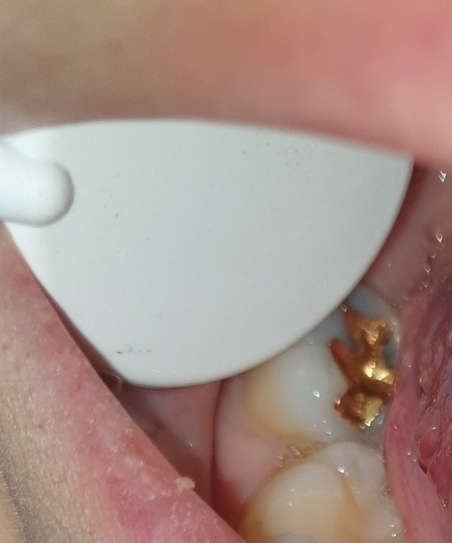

사진으로 볼 때는 큰 충치가 있어 보이지는 않습니다. 치아에 너무 많은 힘이 가해지면 이상이 없음에도 불구하고 불편감이 있을 수 있기 때문에 치아에 가해지는 힘을 줄여보는 것이 좋습니다.

보철물을 제거해봐야 확실하겠지만 충치가 있는 것으로 보입니다. 통증이 지속되면 치료받으러 가셔야 겠습니다.